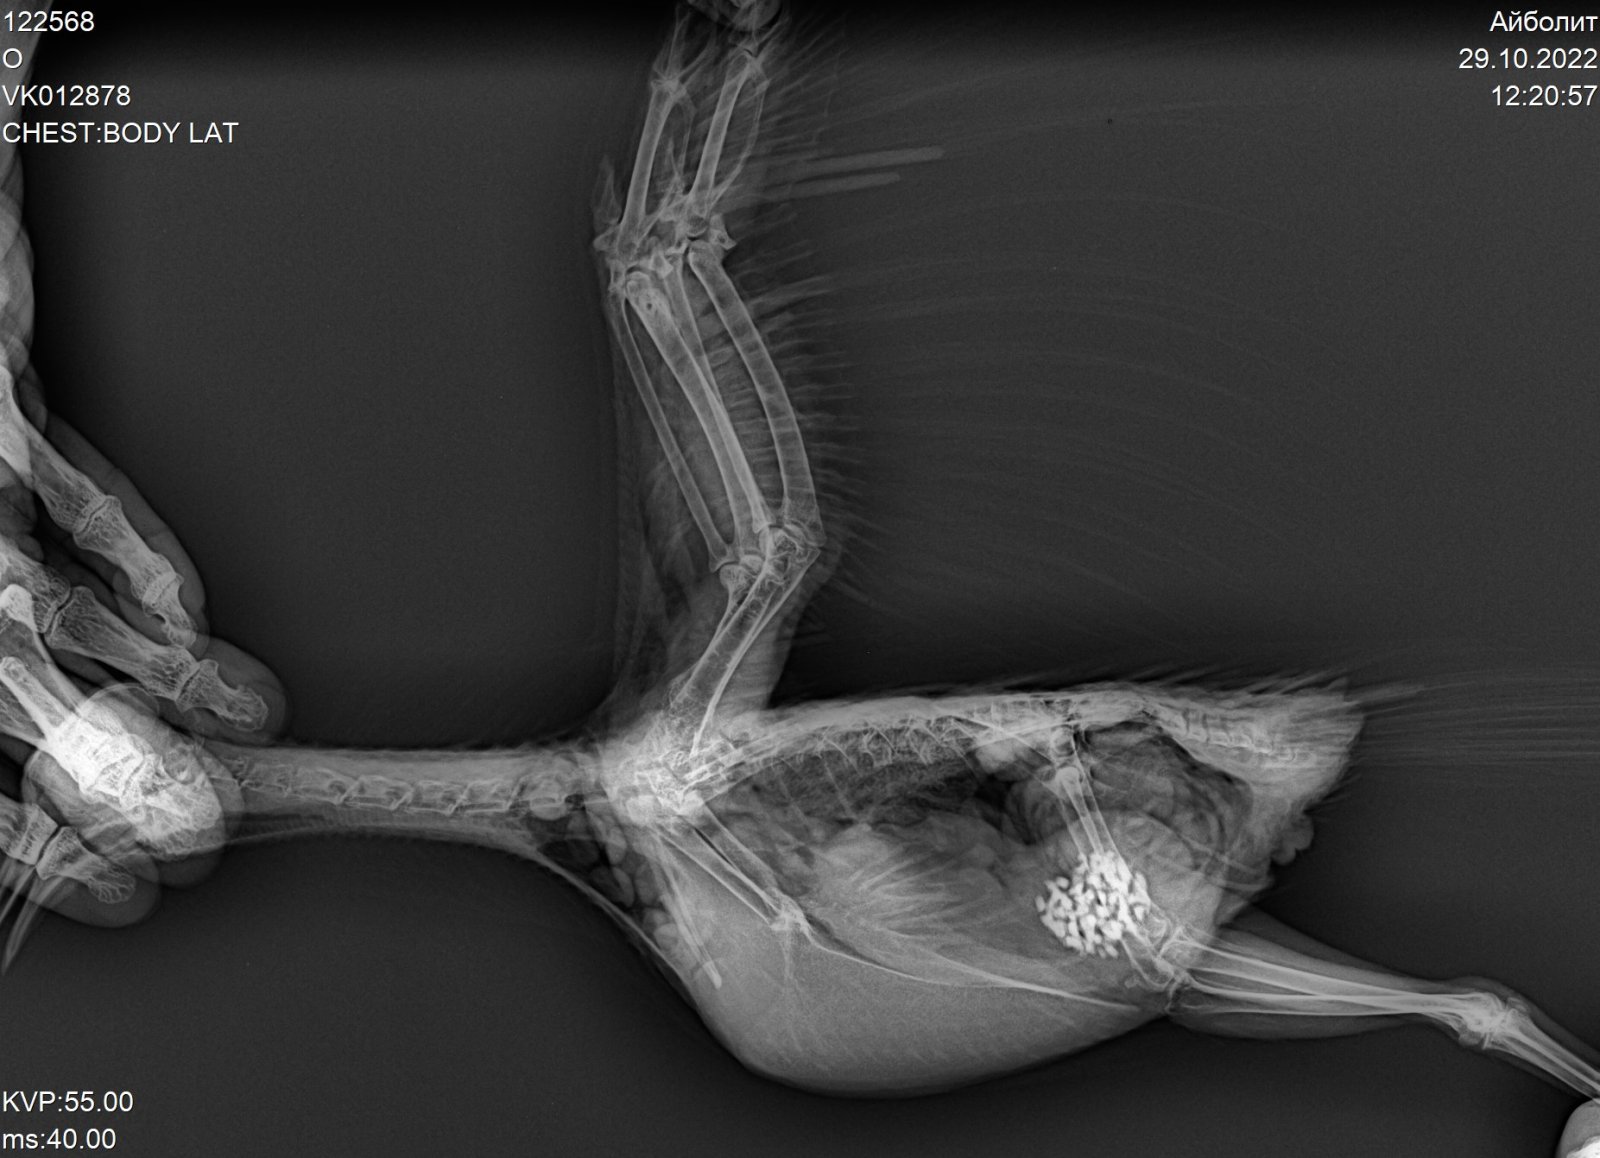

Tanya857 Опубликовано 29 октября, 2022 Автор #86 Опубликовано 29 октября, 2022 Добрый день!Шишка у Петьки отсохла и отвалилась.Летает он сейчас уже очень хорошо,залетает спокойно и на шкафы.Съездили к орнитологу сегодня,устал бедный после такой долгой дороги,но вёл себя на удивление хорошо.Крылышки осмотрели,сделали рентген.Перелома нет,только травма крыла.Ципрофлоксацин не стали менять,единственное сказали разводить немного по-другому 1/2 табл развести на 2,5 мл воды,и внутрь давать по 0,15 мл.Вместо Пимафуцина назначили Флуконазол(1/10 капсулы 2р в день). И ещё в течении 3х дней суспензию «стоп-кокцид» @Анна1972 Спасибо!Поняла?Поищу лучше как у вас силимар, может тоже будет сам клевать. По ципрофлоксацину постараюсь соблюдать интервал. 2